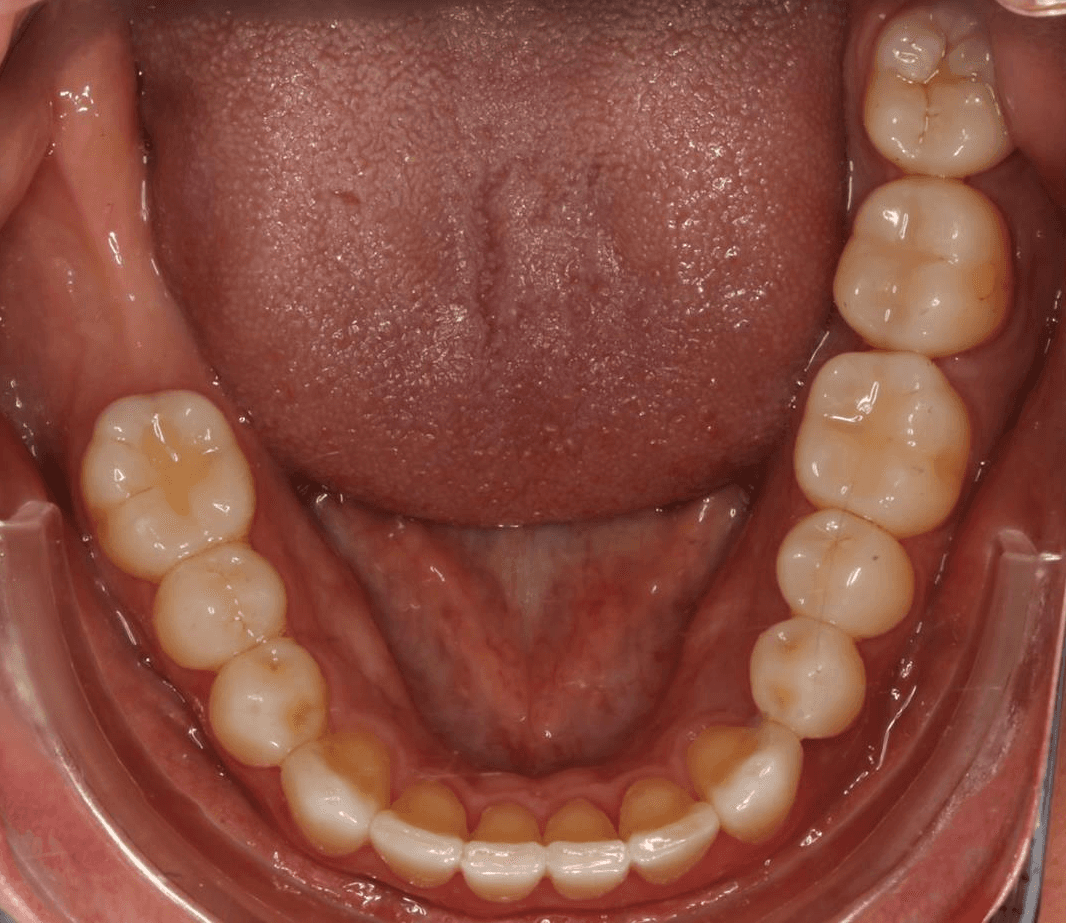

Final results

INTRAORAL